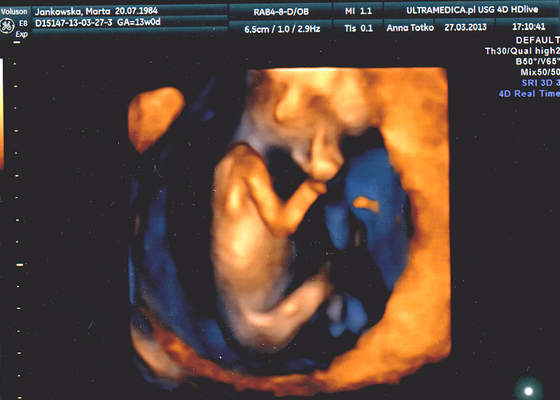

a to moje maleństwo:D